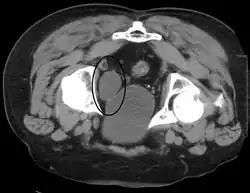

Incontinence and retention

Urinary bladder (black butterfly-like shape) and hyperplastic prostate (BPH) visualized by medical ultrasound

Frequent urination can be due to excessive urine production, small bladder capacity, irritability or incomplete emptying. Males with an enlarged prostate urinate more frequently. One definition of an overactive bladder is when a person urinates more than eight times per day.[28] An overactive bladder can often cause urinary incontinence. Though both urinary frequency and volumes have been shown to have a circadian rhythm, meaning day and night cycles,[29] it is not entirely clear how these are disturbed in the overactive bladder. Urodynamic testing can help to explain the symptoms. An underactive bladder is the condition where there is a difficulty in passing urine and is the main symptom of a neurogenic bladder. Frequent urination at night may indicate the presence of bladder stones.

Disorders of or related to the bladder include:

Disorders of bladder function may be dealt with surgically, by redirecting the flow of urine or by replacement with an artificial urinary bladder. The volume of the bladder may be increased by bladder augmentation. An obstruction of the bladder neck may be severe enough to warrant surgery. Ultrasound can be used to estimate bladder volumes.[31][32]